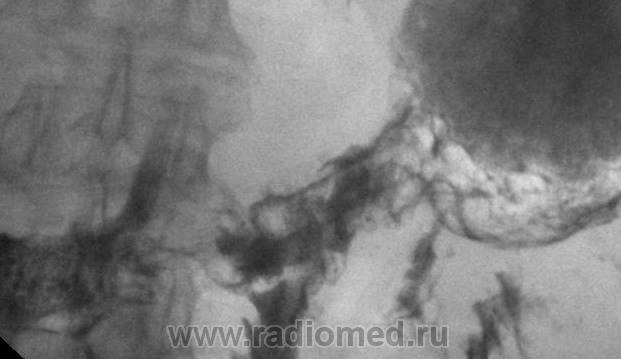

Изображение Вашему вниманию представлены фрагменты серийной цифровой сьемки во время сегодняшней рентгеноскопии ЖКТ.

Пациент: мужчина, 93 года, малоподвижен, состояние средней тяжести, иссследование в вертикальном положениии невозможно, на животе - с трудом. Клинически - одышка, тахикардия, асцит.

Рентгенологически - слева базально - латеральный осумкованый плеврит.

Вопрос- что с антральным отделом желудка?

ФГДС невозможно ввиду противопоказаний, в первую очередь со стороны кардиолога.

Предварительно, я подчеркиваю предварительно, теневая картина рака желудка, с преимущественным поражением антрального отдела, возможно с преобладанием скиррозного (фиброзного) компонента. Более детально, несколько позднее.

Налицо сужение антрального отдела желудка, "относительная" ригидность стенок суженного участка, трансформация рельефа слизистой оболочки по типу "атипического" рельефа - все признаки злокачественного процесса. Следовательно дифференциальную диагностику целесообразно проводить только с ригидным антральным гастритом.

Но, если детально проанализировать "трансформированную" слизистую оболочку пораженного участка, то, увы, "РИГИДНОМУ АНТРАЛЬНОМУ ГАСТРИТУ" шансов не остается, все говорит о раковом процессе.

Об этом пока и речи нет, дедульке 93 года, уже по возрасту - 5группа риска...не могу убедитьдаже на ФГДС для биопсиии - утверждают, что "серце не выдержит"...+ асцит. Эндоскопист согласен, но только после парацентеза. Кардиологи чешут пока репу.Как по мне, то инфильтративная форма рака, но ведь и антральный ригидный гастрит нельзя полностью сбрасывать со счетов. Жаль, что не могу Вам воспроизвести серийную сьемку..."функциональное поведение" антрального и препилорического отделов весьма двойственно. С одной стороны - ригидность, с другой, достаточно активная перистальтика......

Таким образом, считаю, ригидность стенок и сужение большей части антрального отдела не вытекает из серии рентгенограмм, атипизм рельефа тоже как-то неочевиден. Здесь скорее сглаженность рельефа слизистой. Так ведь лет-то 93! Слизистая – атрофична и на лице у него складки, пожалуй, рельефнее должны быть. Да и контраст, похоже, малоконцентрированный.